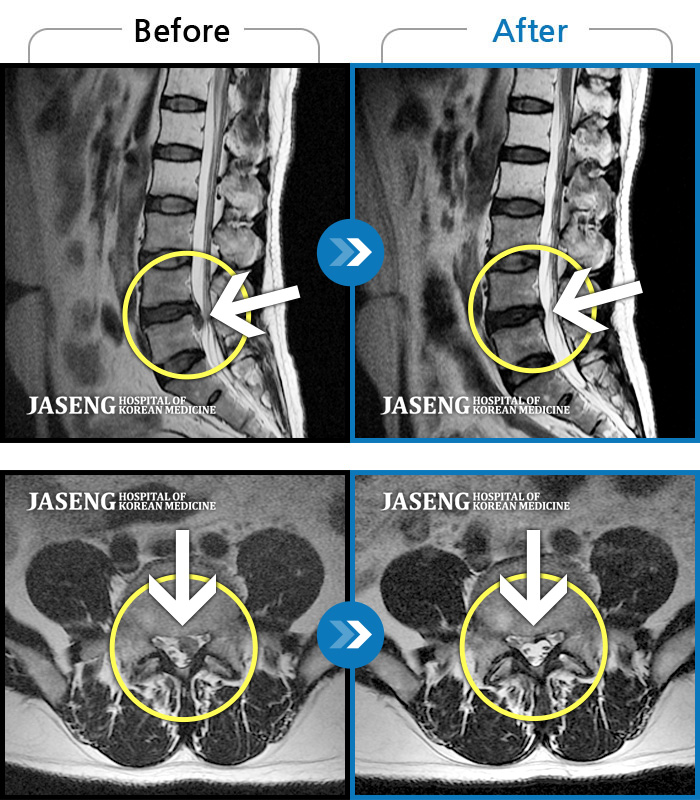

허리통증이 심해서 숙이기 어렵고 차에서 내리기 힘들었습니다.

2021.01.06 ~ 2025.03.10